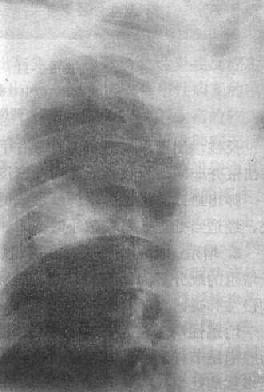

2)右肺中叶不张:较为常见,后前位表现为右肺下野内侧靠心右缘现上界清楚下界模糊的片状致密影,心右缘不能分辨(图3-1-9)。侧位上表现为自肺门向前下方倾斜的带状或尖端指向肺门的三角形致密影(图3-1-9)。上、下叶可有代偿性肺气肿。

图3-1-9 右肺中叶肺不张(正、侧位)